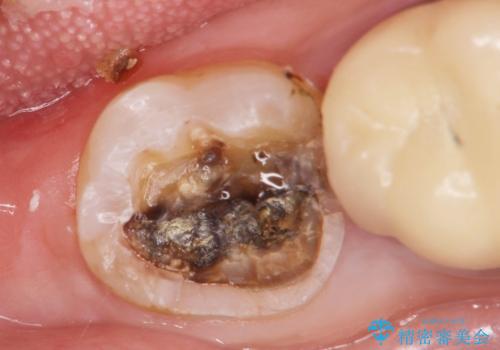

視診にて、インレーの破折、インレー下に虫歯が再発していることを認めました。

壊れてしまったインレーおよび、虫歯を神経を温存できるよう丁寧に除去したのち、耐破折に優れるセラミッククラウンで再補綴治療を行います。

再発した虫歯は小さくなかったものの、丁寧に虫歯をとることで神経を温存することができました。